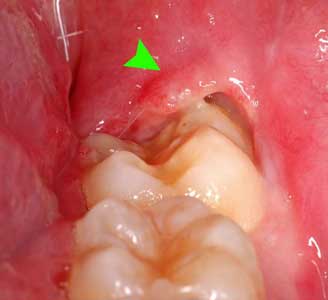

• Gum around the last tooth may get swollen and red; sometimes pus comes out if an abscess develops.

Infection in Wisdom Tooth

This can be very painful, and trapped wisdom teeth have a tendency to develop infections, abscesses or swelling. This also decrease mouth opening when that happens, they need to be removed as soon as the infection is under control.